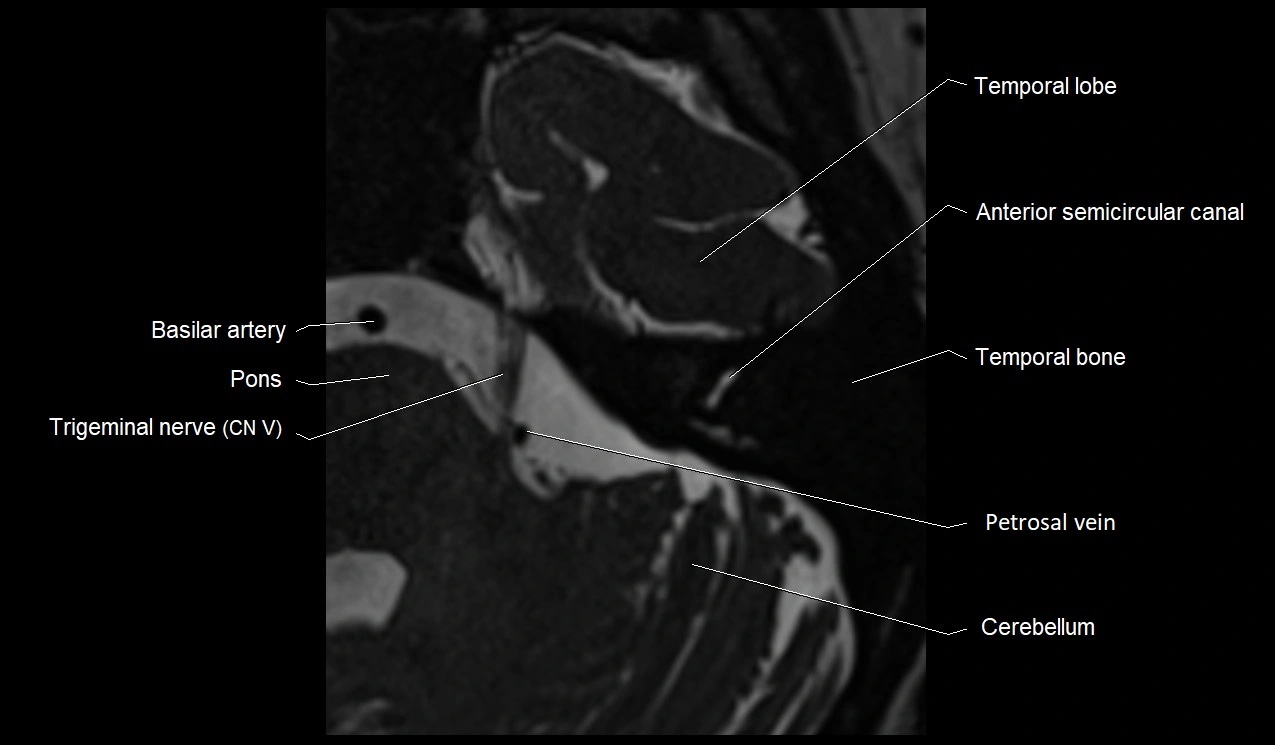

MRI images

image